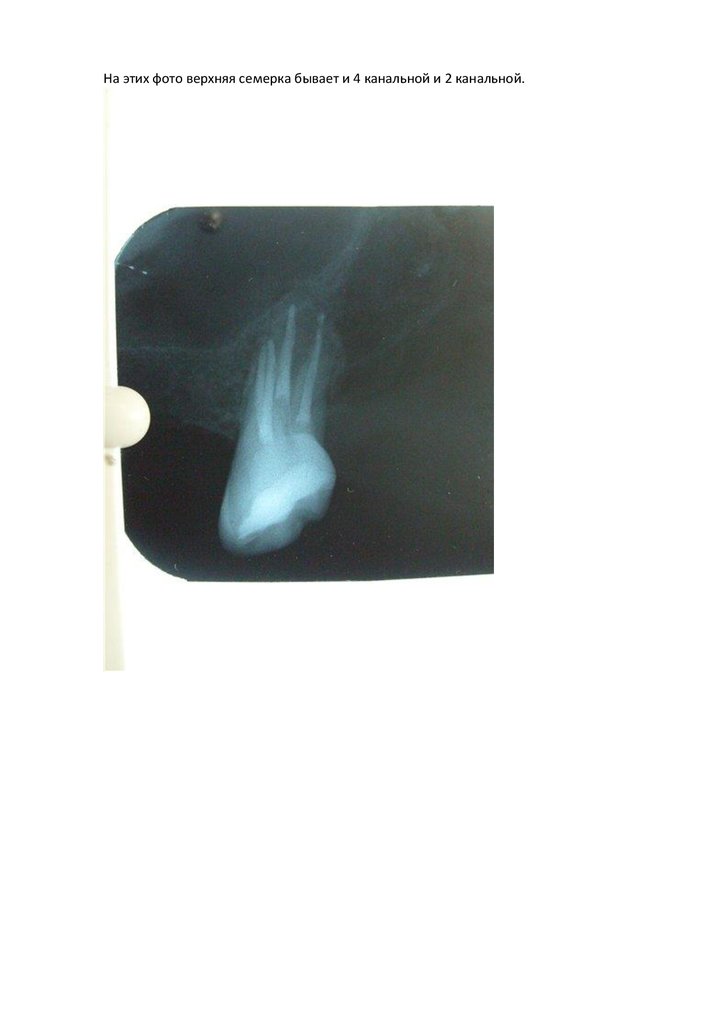

На этих фото верхняя семерка бывает и 4 канальной и 2 канальной.